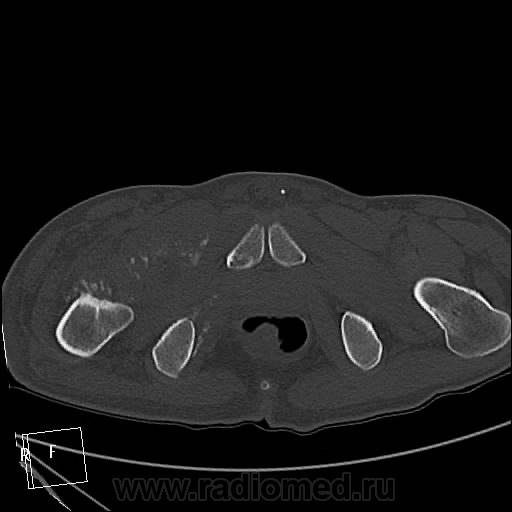

Мужчина 37 лет. Травму отрицает. Верификации нет, и неизвестно, будет ли. Думаю на остеосаркому. Характерно ли такое распространение до L3?

Лежал около месяца в другом ЛПУ, парез, отек конечности, преходящий парез другой конечности, худеет, слабость. К нам однократно в январе привозили на КТ головного мозга для исключения инсульта - исключили. Поступил вчера, в направлении "заболевание спинного мозга?", направлен на КТ грудного и поясничного отдела и таза для исключения мтс в позвоночник и перелом шейки правого бедра. В позвоночнике деструкции не нашла. Анализов пока тоже нет. Температура в норме.

ЗНАЧИТ ТАК - ТУТ ИМЕЕТ МЕСТО ПАТОЛОГИЧЕСКИЙ ПЕРЕЛОМОВЫВИХ В ОБЛАСТИ ПРОКСИМАЛЬНОГО ЭПИМЕТАФИЗА ПРАВОЙ БЕДРЕННОЙ КОСТИ !!САМ ПРОЦЕСС СКОРЕЕ ВСЕГО КАК С ОСТЕОЛИТИЧЕСКИМ ,ТАК И ОСТЕОБЛАСТИЧЕСКИМ КОМПОНЕНТОМ С ПРЕОБЛАДАНИЕМ 1-ГО.ИМЕЕТСЯ МЯГКОТКАННЫЙ КОМПОНЕНТОМ С УЧАСТКАМИ ПОНИЖЕННОЙ ПЛОТНОСТИ и обызвествлениями,разбросанными по периферии!!ПО ПЕРЕДНЕ ЛАТЕРАЛЬНОМУ КОНТУРУ ВЕРХНЕЙ ТРЕТИ ДИАФИЗА И МЕТАФИЗА БЕДРА ОПРЕДЕЛЯЕТСЯ ИГОЛЬЧАТЫЙ ПЕРИОСТИТ. В ПРОЕКЦИИ ЭПИМЕТАФИЗА ОПРЕДЕЛ-СЯ МНОЖЕСТВЕННЫЕ ФРАГМЕНТЫ РАЗНОЙ ДЕНСИМЕТРИЧЕСКОЙ ПЛОТНОСТИ/вдоль повздошных сосудов по задней и паравертебрально определяется инфильтрация восполительная или опухолевая.?местами ограниченные участки с низкой плотностью ,конгломерат увел лимфат -ких узлов ?с включениями извести в проекции крыла повздошной кости и повздшно поясничной мышцы.перелом патологич в области седалищной кости и крыши вертлужной впадины с остеолитическим компонентом ,в теле повздошной кости участок деструкци и со склеротической каймой !!

мой диагноз ходросаркома ,которая в отличие от остеосаркомы часто встречается в метаэпифизе бедренной кости+возраст 37лет тоже в пользу 1 ой.на счет перелома он патологический !!!даже если на данный момент нет шейки и головки !просто странно что только сейчас к вам направляют на потдверждение перелома .на счет вывиха даже в случае полного разрушения верхняя треть диафиза не там где нужно,смещена латерально и кзади ,на счет игольчатого периостита ,это конечно мое мнение пересмотрите 5срез в аксиальном костном режиме и 2 во фронтальном .и кстати на пятом в просвете прямой кишки определяется экзофитно растущее образование ? скорее всего это какашка извиняюсь за выражение но все же перепроверте может и то что мне кажется)))))ну и не нравится зона в проекции повздошно поясничной,повздошной и большой поясничной мышц с включениями извести и сниженной денситометрической плотностью ограниченных участков в центре .это может поменять диагноз первичного поражения мышц (саркома ) на кость вторично!предлагаю законтрастировать кишечник и сделать контрастное исследование (болюс)и посмотреть -что за природа этого участка .?

второй диагноз рабдомиосаркома,характеристика участки 1некроза и кистовидного перерождения2имеют разнообразуню локализацию3обызвествления 4 переход на кость с массивными участками деструкции4заметный солидный компонент усиливающийся при контрст исслед.

в 85% случаев поражается бедро